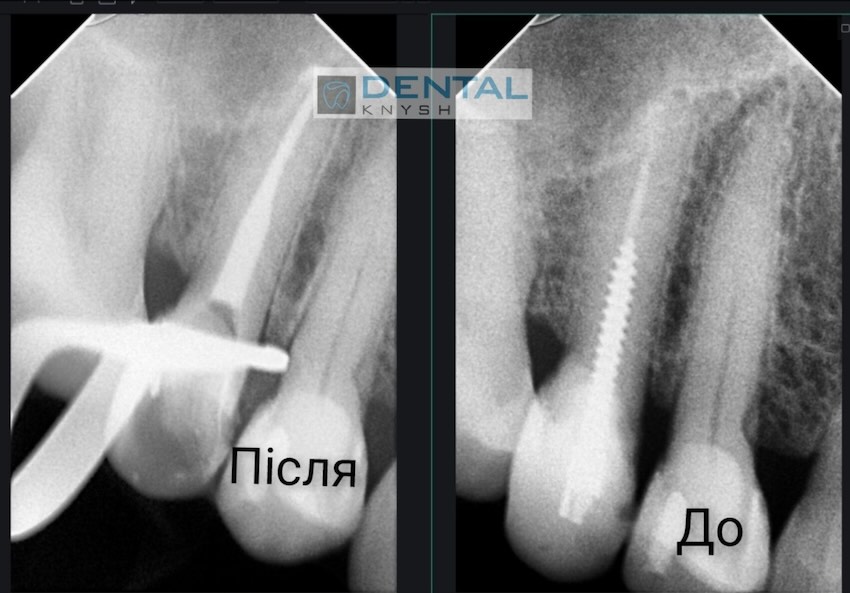

Лікар-ендодонтист Вадим Петриченко спеціалізується на лікуванні зубних каналів під мікроскопом.

Фото звіти

Більше фото звітів можна подивитися на сторінці Лікування зубів під мікроскопом